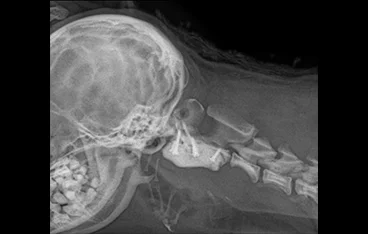

신경계종양(뇌&척수종양)

종양절제술

• 뇌종양